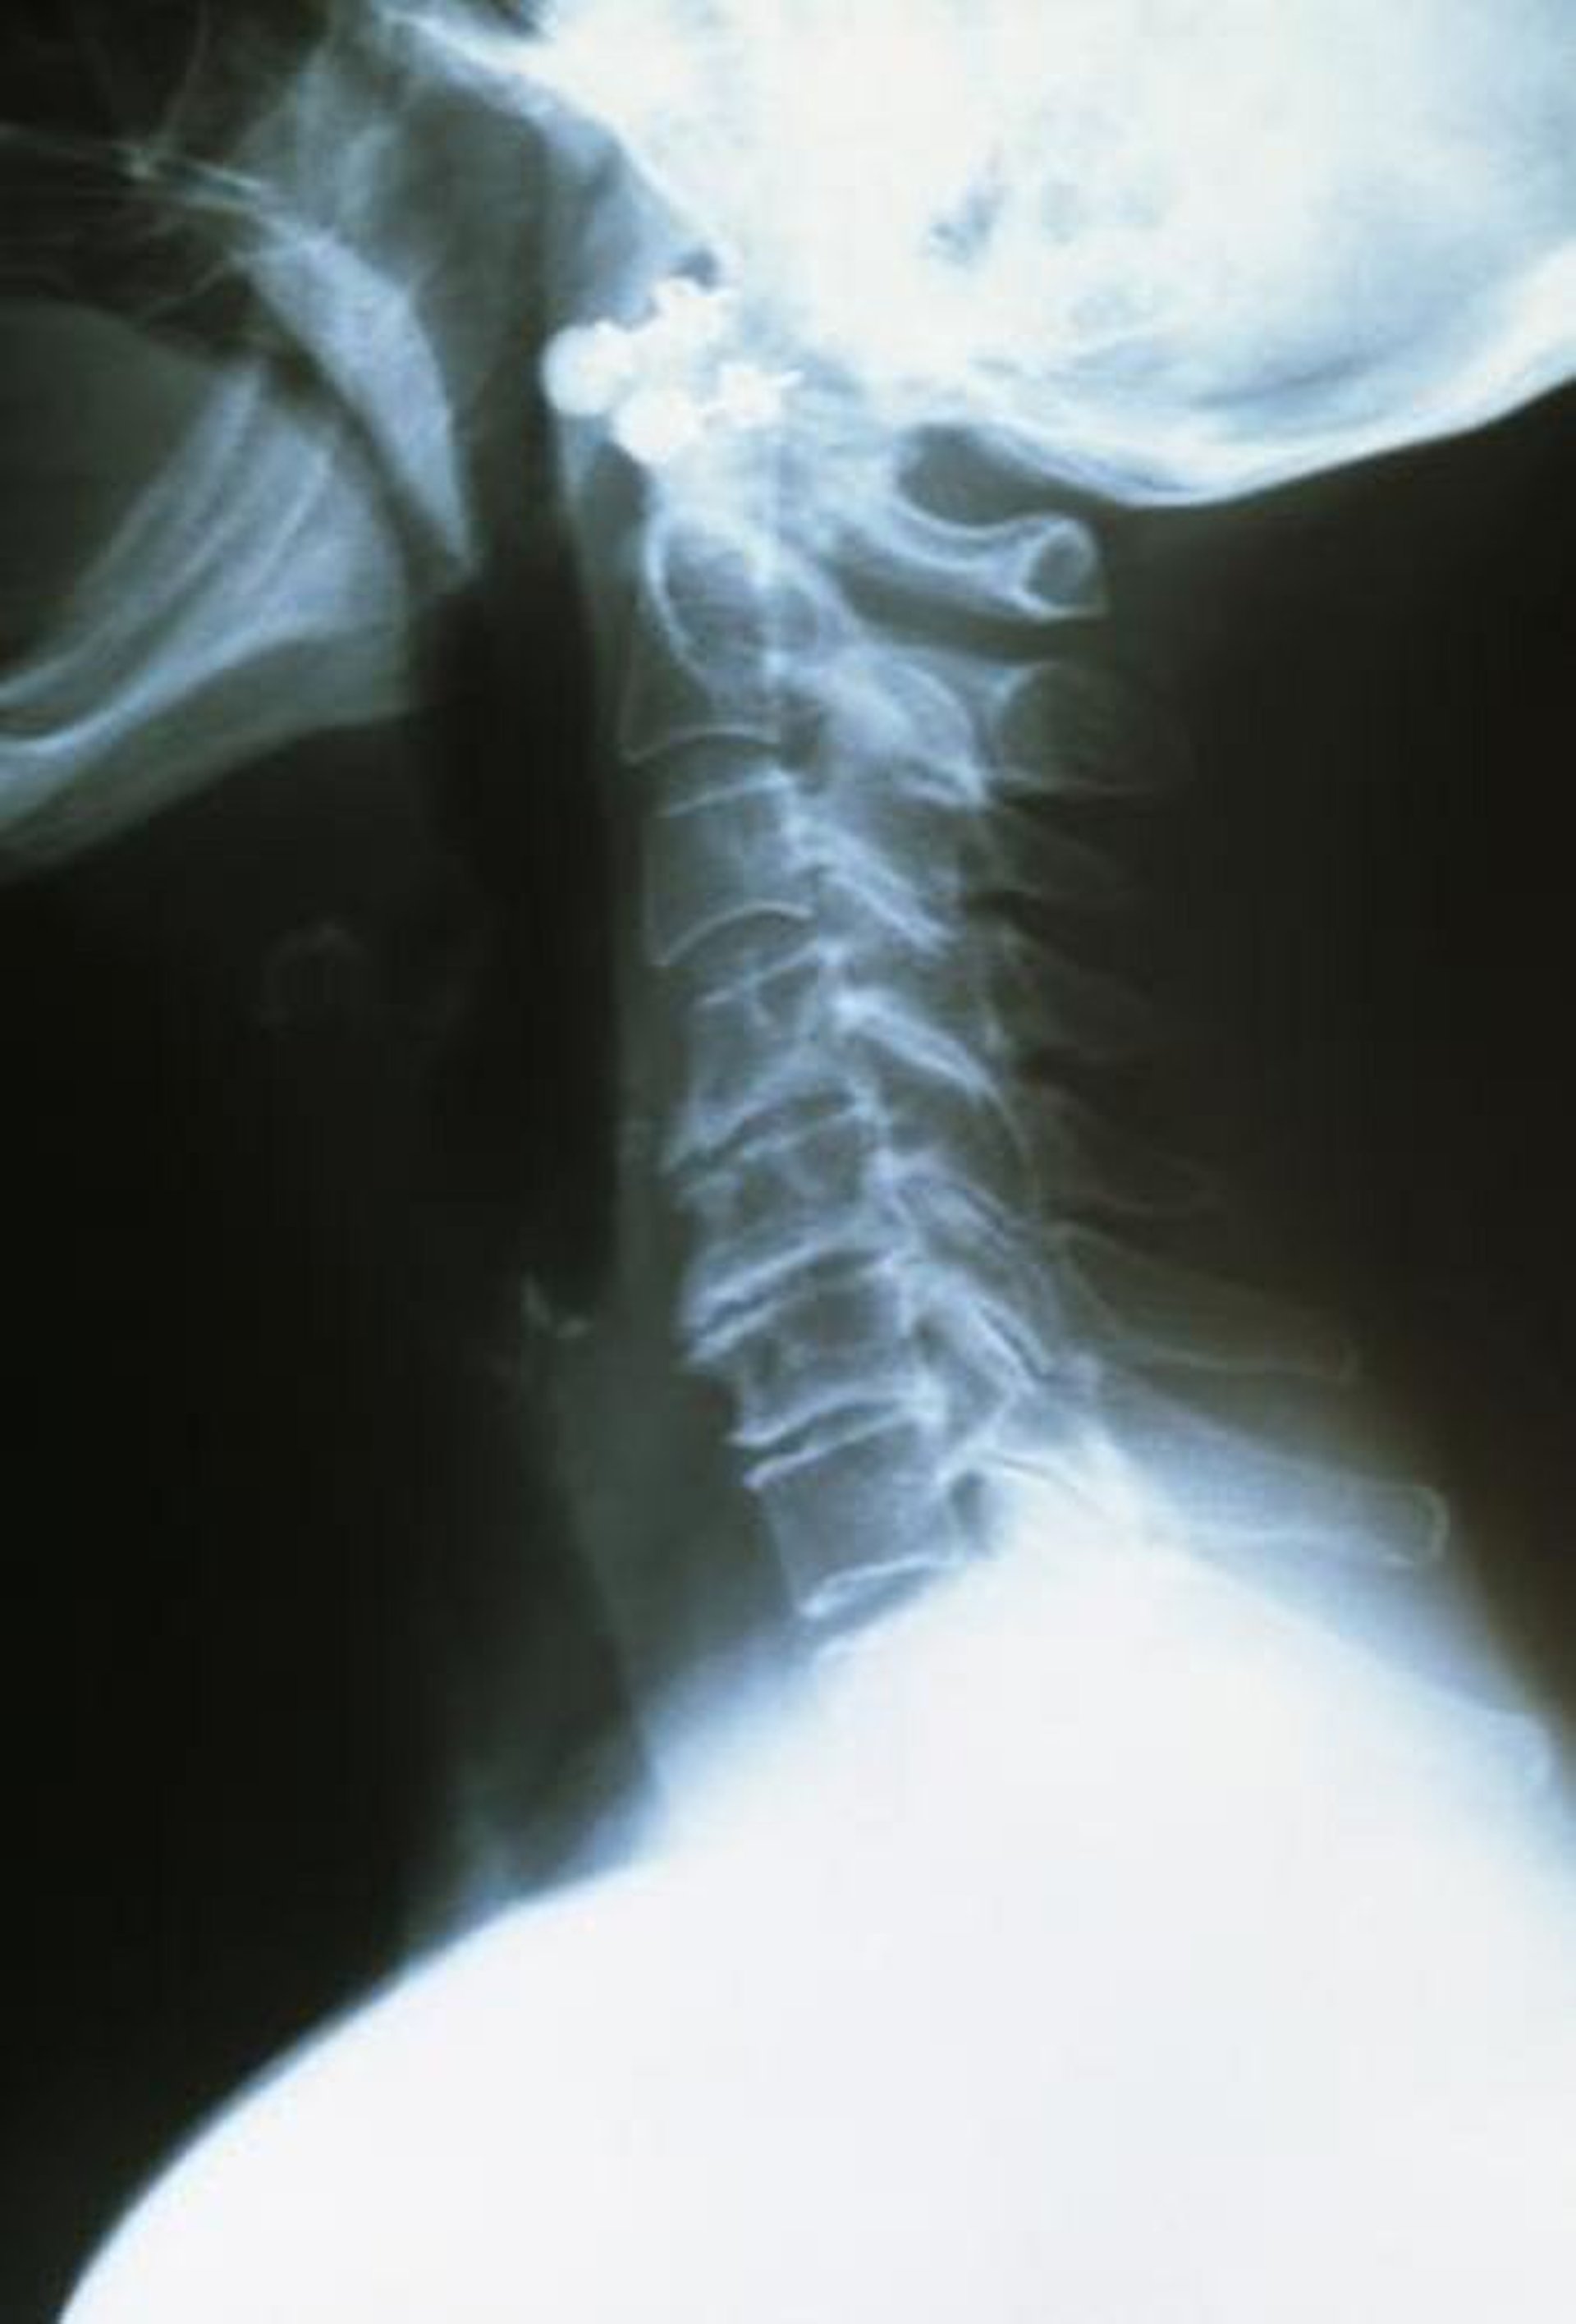

Шийний остеоартрит

The upper cervical vertebrae are healthy, well spaced, and smooth edged. The arthritic lower vertebrae are closer together and have rough and ragged edges.